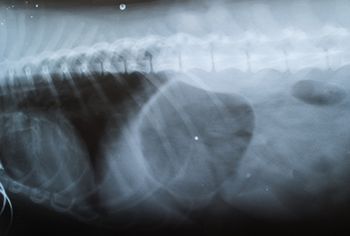

This dog was referred to an oncologist because of a mass identified by its primary veterinarian. Work through this case with the team at the University of Tennessee to find out what happens once a patient is referred.

Examine the ultrasonograms, study the exam findings, and see if you can name the cause in this feline patient with hematuria and recurrent UTIs.

An intervention to remove urinary stones didn't alleviate this bichon frises's stranguria. See if you can spot the cause in this ultrasonogram.